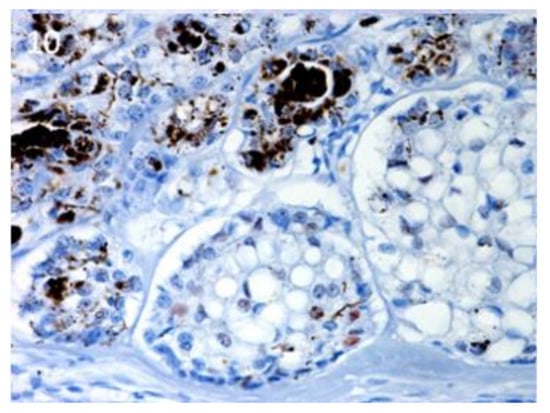

3.3. Stem Cell Marker Analyses in Hair Follicle Tumours. TB Samples Show the Highest mRNA Expression of Lgr6, Lgr5 and Sox9, that are Potentially Useful Markers in Differential Diagnosis with BCC